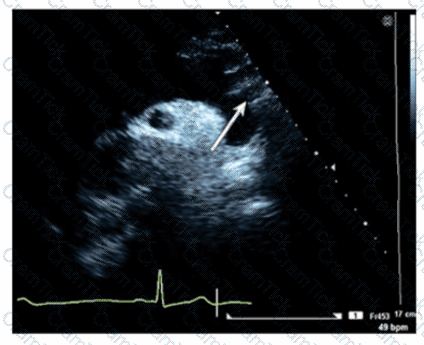

Which left ventricular regional wall segment is indicated by the arrow on this image?

Which condition is most plausible based on the finding indicated by the arrow on this image?